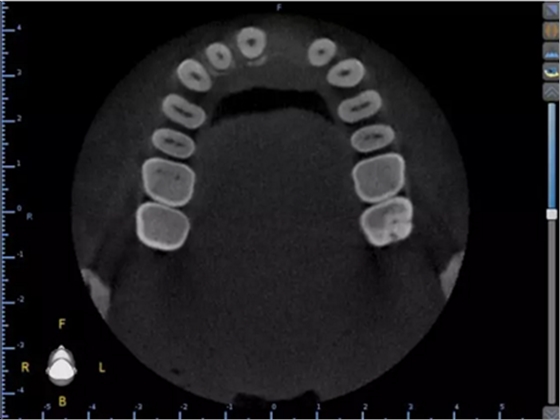

1.術(shù)前CT

2.術(shù)前植體設(shè)計(jì)

3.術(shù)前導(dǎo)板設(shè)計(jì)

術(shù)后CT